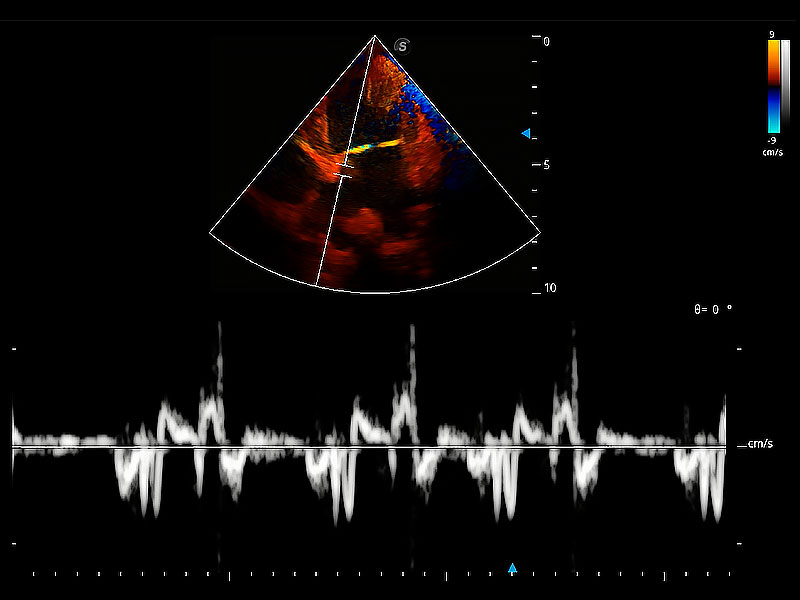

實時用顏色表示心肌組織運動,觀察和定量組織的運動情況,對快速檢測與評估心肌的灌注和活性、電傳導及心肌收縮和舒張功能等均能提供重要的診斷信息。